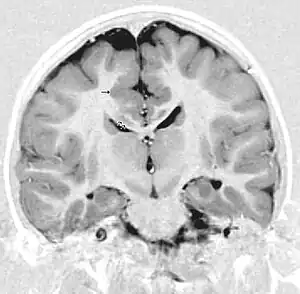

| This child presented with seizures. The coronal true inversion recovery sequence shows thickened and disordered cortex in superior frontal and cingulate gyri bilaterally (arrow). There are small convolutions visible at the corticomedullary junction. The appearance is that of cortical dysplasia, with polymicrogyria more likely than pachygyria due to the small convolutions visible. There are also small foci of grey matter signal in the corpus callosum, deep to the dysplastic cortex (double arrows). These probably represent areas of grey matter heterotopia. | |

Pathologically, PMG is defined as "an abnormally thick cortex formed by the piling upon each other of many small gyri with a fused surface."[14] To view these microscopic characteristics, magnetic resonance imaging (MRI) is used. First physicians must distinguish between polymicrogyria and pachygyria. Pachygria leads to the development of broad and flat regions in the cortical area, whereas the effect of PMG is the formation of multiple small gyri. Underneath a computerized tomography (CT scan) scan, these both appear similar in that the cerebral cortex appears thickened. However, MRI with a T1 weighted inversion recovery will illustrate the gray-white junction that is characterized by patients with PMG.[13] An MRI is also usually preferred over the CT scan because it has sub-millimeter resolution. The resolution displays the multiple folds within the cortical area, which is continuous with the neuropathology of an infected patient.